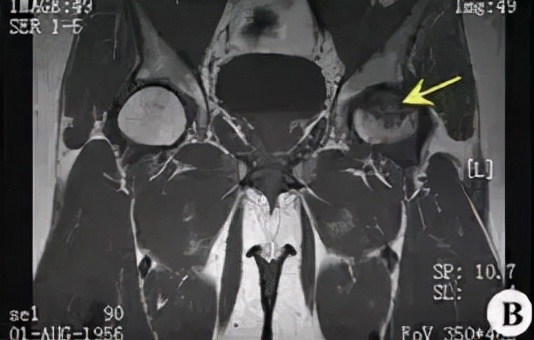

磁共振: 是一种有效的非创伤性的早期诊断方法。

大多表现为股骨头前上部异常信号:T1为条带状低信号;T2为低信号或内高外低两条并行信号影,即双线征(double line sign)。双线征中外侧低信号带为增生硬化骨质,内侧高信号带为肉芽纤维组织修复所致。